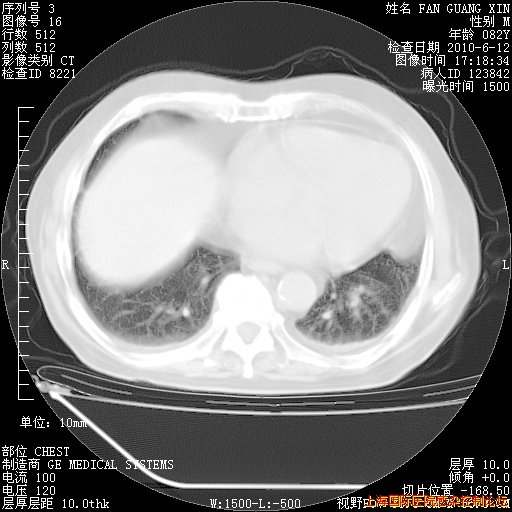

整整相隔30天的肺部CT好像有所好转啊。甲强龙减量第3天,需要观察体温。

海管,自昨日你和我通完话后,不知您岳父消化道症状有无缓解?体温怎样?阅读7.12日胸部ct,个人认为目前激素治疗是有效的,甲强龙减量是适宜的。因在抗痨治疗,需密切观察肝功、肾功能和血常规。不过,老年、长期住院和大量使用激素,很担心菌群失调发生